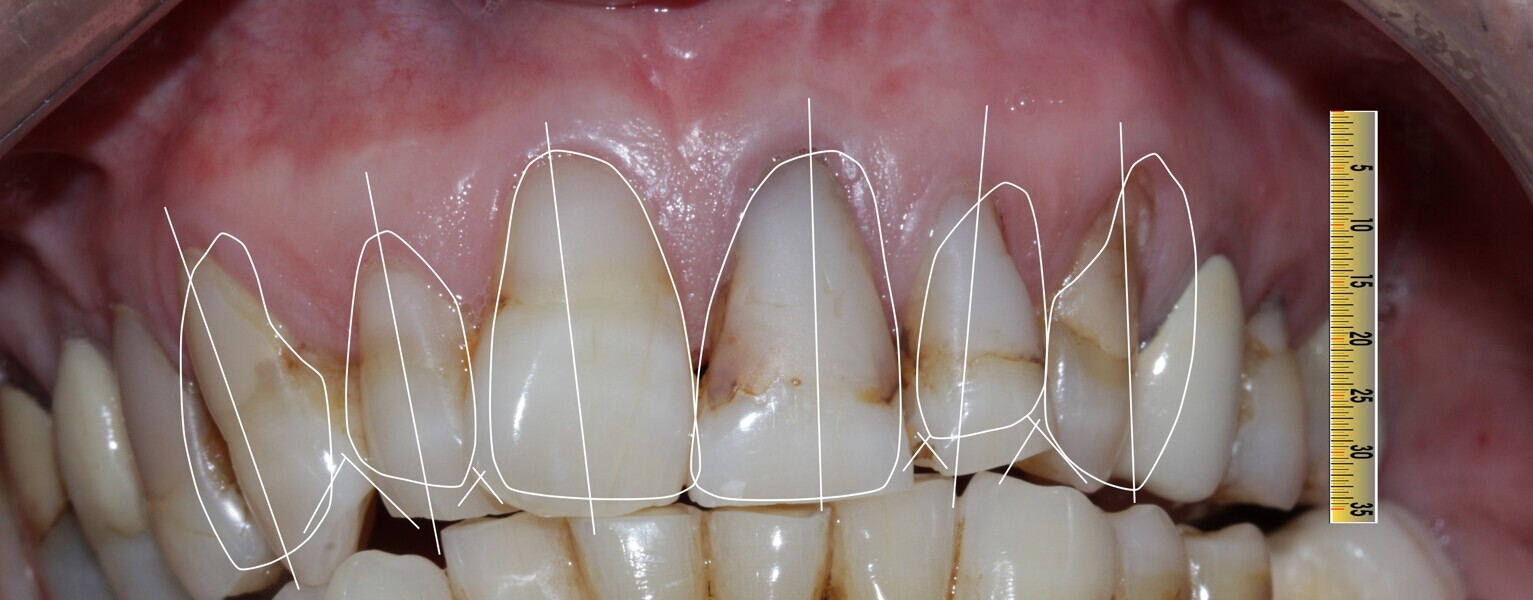

Figure 10 Digital smile desinging planning

Figure 11 Digital smile designing planning